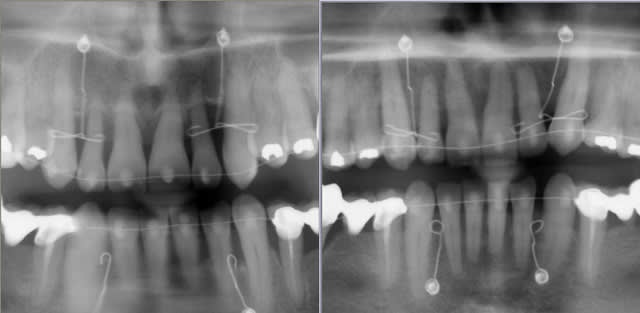

Ce qui est intéressant dans ce cas, c'est que l'ingression s'est accompagnée d'un recul radiculaire des incisives non explicable par la mécanique utilisée (très simple par ailleurs).

Le fil que j'avais utilisé était rond, ce n'est pas lui qui a pu reculer les racines.

Ce n'est pas non plus l'effet de la direction de la force d'ingression, comme je le montre sur le schéma. On aurait dû avoir une vestibuloversion coronaire pas un recul des apex. Le centre de résistance de la dent était très haut parce qu'il y avait un support osseux très réduit.

Il faut donc chercher ailleurs l'explication, et c'est là qu'on pourrait faire un parallèle avec le cas de Jeff…

Ce que j’ai voulu monter avec le cas d’ingression c’est l’action méconnue de l’orbiculaire des lèvres. Je ne vois pas d’autre explication à ce recul des apex qu’une pression de sa part sur la corticale vestibulaire et un « glissement » de la racine le long de cette corticale.

À rapprocher de l’importante fenestration qu’on peut observer sur son cas à toi.

Ce résultat ne pouvait d’autre part avoir lieu qu’en laissant les dents s’orienter toutes seules et donc en proscrivant tout système traditionnel qui cherche à contrôler les racines. C’est tout l’intérêt des danchamons qui donnent de la liberté aux dents tout en leur indiquant une direction avec des forces très légères, applicables même dans des cas paro très dégradés...